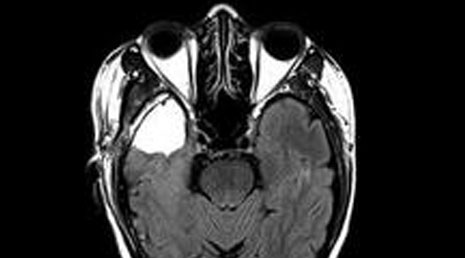

58. Subependymoma